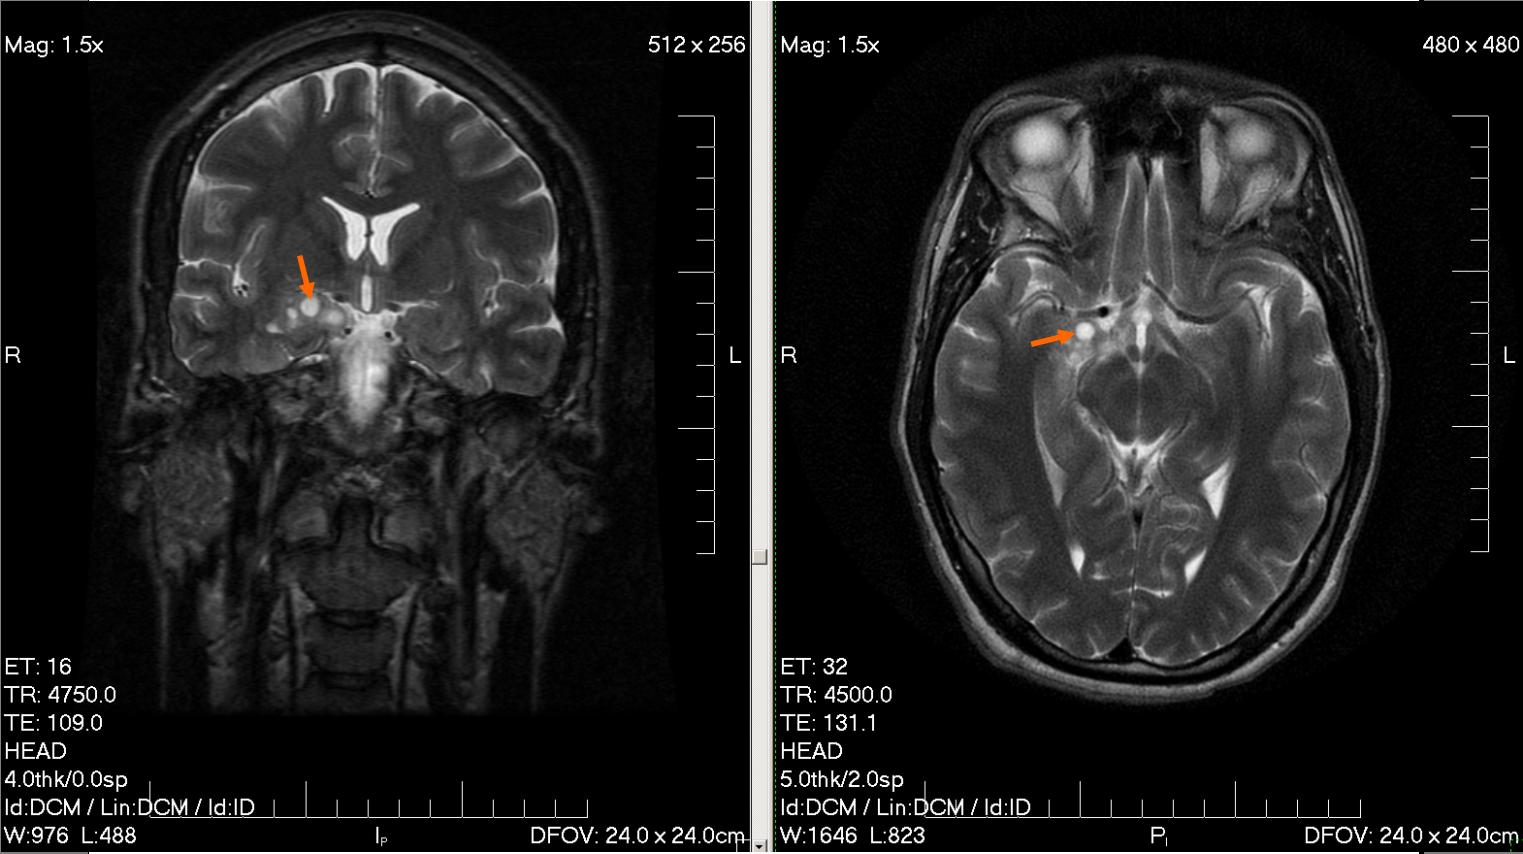

Concernant l’étude CERENAT à proprement dite, elle a été réalisée par l’université de bordeaux, publié le 9 mai 2014 dans la revue scientifique Occupationnal et Environnemental Medecine. Elle porte sur une cohorte de 1339 personnes dont 447 personnes ont été atteintes soit de gliomes ou de méningiomes entre 2004 et 2006 dans les départements du Calvados, Gironde, l’Hérault et la Manche. Après une enquête auprès des personnes malades, ou de leurs proches en cas de décès, sur leur consommation de téléphone portable, les auteurs de l’étude ont comparé la prévalence de ces cancers entre le groupe témoin non-utilisateur de téléphonie mobile et les malades. Aucune différence statistique notable a été révélée entre les deux groupes (OR=1.24; 95% CI 0.86 to 1.77 pour les gliomes, OR=0.90; 95% CI 0.61 to 1.34 pour les méningiomes). En revanche les utilisateurs ayant cumulé plus de 896 heures au cours de leur vie ont d’après cette étude quasiment 3 fois plus de chance d’avoir un gliome (OR=2.89; 95% CI 1.41 to 5.93) et 2.5 fois plus de chance d’avoir un méningiome (OR=2.57; 95% CI 1.02 to 6.44). En extrapolant, ceux qui consommeraient plus de 15 heures par mois, soit plus de 30 minutes par jour auraient plus de chance de développer ce type de tumeurs.

Au final tout ça pour dire que ce genre d’étude ne servirait qu’à alimenter la phobie d’une minorité et qu’il n’y aucun problème avec la technologie des radiofréquences. Sauf que cette étude même si à elle toute seule ne révèle rien, elle converge dans le même sens que celle d’Interphone ou encore d’une étude Danoise et qui ont débouché sur la classification des radiofréquences comme possiblement Cancérigène par l’OMS. D’ailleurs la justice dans certains pays commence à prendre le problème au sérieux comme avec cet Italien, Mr Marcolini dont sa tumeur située au niveau du nerf trijumeau a été reconnue comme consécutive de son exposition aux radiofréquences, une class action est organisée en ce moment même par 29 personnes ayant déclarées une tumeur au cerveau aux Etats Units. Finalement je suis un peu déçu de cet article de Canard PC, surtout qu’au lieu de ne faire que des critiques sur l’étude de l’université de Bordeaux, il aurait été judicieux de proposer des solutions alternatives comme imposer aux opérateurs de conserver les temps de conversation de leurs clients tout le long de leur vie comme ça on pourrait avoir une idée plus précise et plus rapide sur le temps passé au téléphone, d’autant plus qu’ils le font déjà sur certaines méta-données qui servent à nous surveiller, donc ce n’est pas impossible à mettre en place, mais ça fait jamais plaisir de se mettre une balle dans le pied …